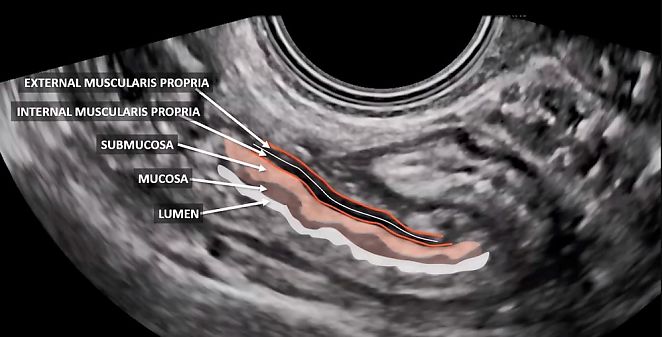

Rectum

The rectum can be evaluated during a transvaginal gynecological pelvic ultrasound, allowing for the identification of the different layers of its wall (Figure 9). Although this assessment is not a routine part of standard gynecological ultrasound, it is essential for patients with endometriosis or oncological pathology. In such cases, it enables the precise determination of the lesion's location and grade of infiltration.

9

Longitudinal section of rectum, showing its layers.

- Rectal evaluation: although rectal assessment is not routinely included in standard gynecological ultrasound, it is essential for patients with endometriosis or oncological pathology. Ultrasound allows for the identification of the different layers of the rectal wall, providing valuable diagnostic information.